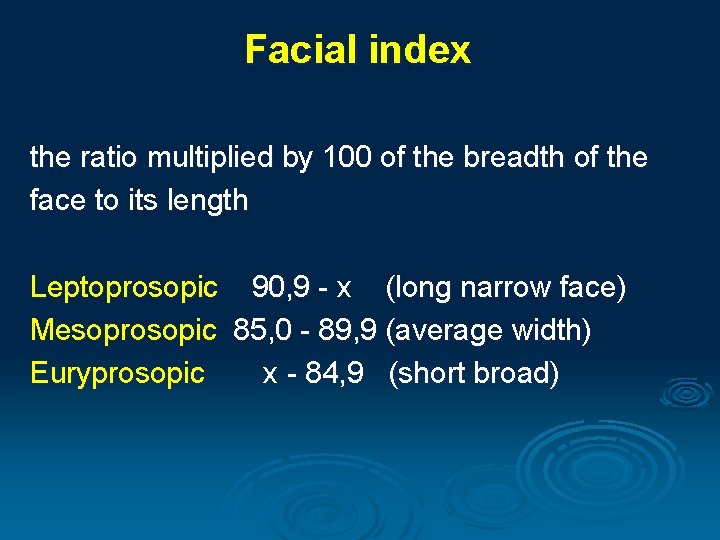

Facial index the ratio multiplied by 100 of the breadth of the face to its length Leptoprosopic 90, 9 - x (long narrow face) Mesoprosopic 85, 0 - 89, 9 (average width) Euryprosopic x - 84, 9 (short broad)